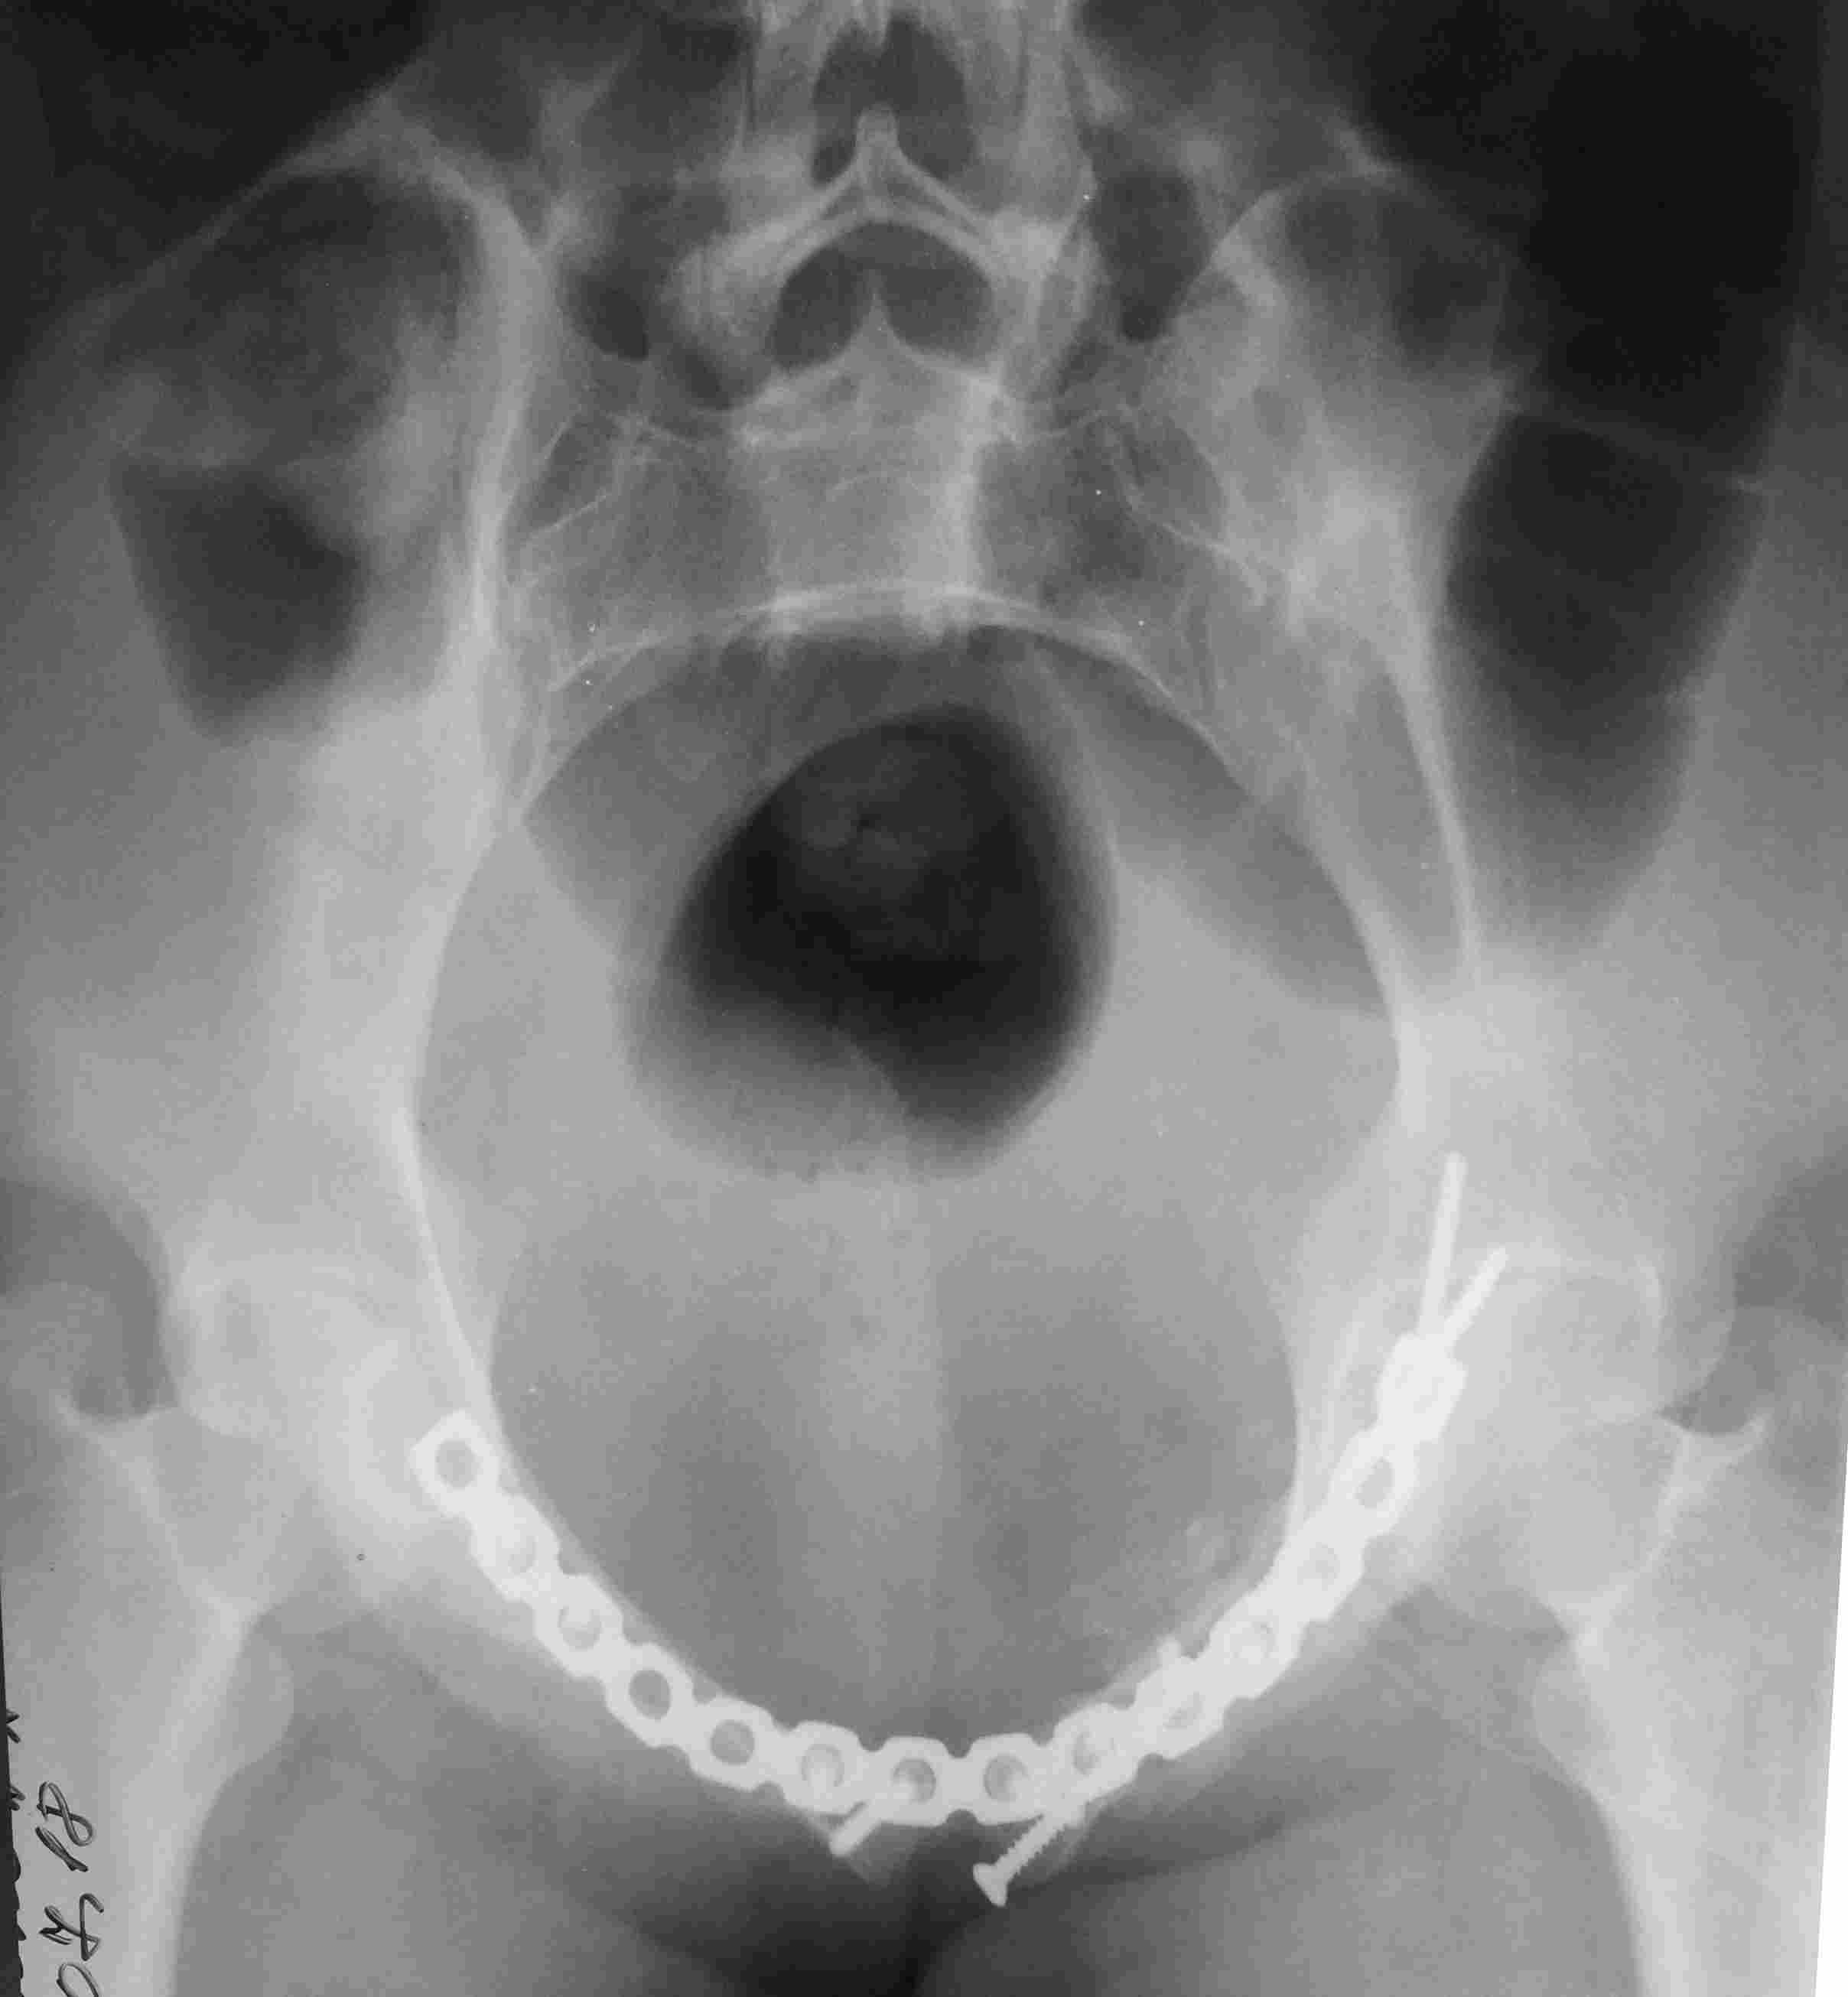

Постоп. Верхняя ветвь возле шейки мочевого пузыря, нижняя так же где-то глубоко в мышцах, ротирована. Обе практически лишены кровоснабжения. лонное сочленение фактически свободно лежащее, справа почти целое, но ветви сломаны возле него. Слева часть лонного сочленения цела на 2/3. интраоперационно подвижность правой половины таза. Постоп все стабильно, но все же планирую дополнительно провести IS винт справа.

PS Нижнюю ветку нормально зафиксировать не получалось зафиксировать, уложил ее в виде чипсов туда, где она примерно была и вдоль верхней ветви слева